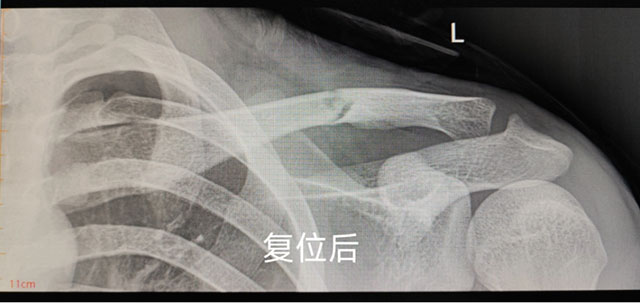

川南在线 发布时间:2024-12-03

CT复查显示复位成功,不需手术

去年12月,泸州一男子爬树时被树枝挂住衣服,从树上跌落,肩部外侧着地导致锁骨骨折。在西南医科大学附属中医医院骨伤科创伤·正骨组经中医正骨手法复位,1月完全恢复。